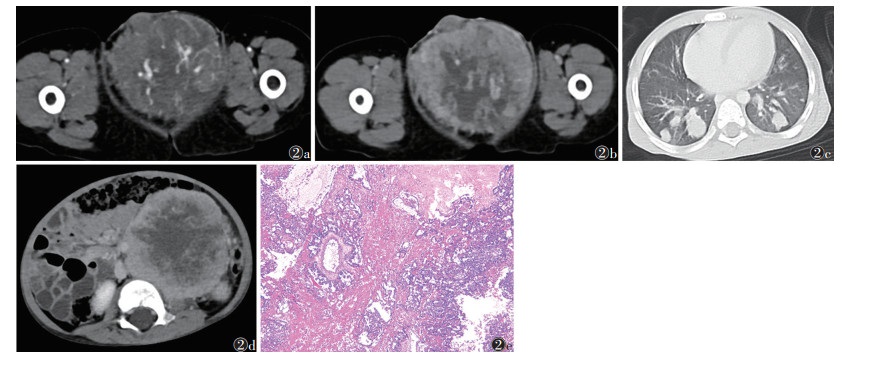

7例中,2例位于右侧睾丸,5例左侧。肿块体积较大,密度不均、形态欠规则,CT值15~45 HU,中心见多发液化坏死区。肿瘤实性成分明显不均匀强化,可见不规则斑片状、结节状、条索状强化影,呈渐进性强化,肿块内坏死区无强化,边界清晰,未见钙化及脂肪成分(图 2)。2例术前已发生远处转移,2例术后1年腹腔多发淋巴结转移。

| 注:患者,男,2岁。图 2a,2b分别为增强扫描动脉期和静脉期图像,示睾丸体积显著增大,可见类圆形肿块,密度不均,中心见大片液化坏死区,动脉期肿瘤实性成分明显不均匀强化,可见不规则斑片状、条索状强化影;静脉期强化持续增加,呈渐进性强化特征;未见钙化及脂肪成分。图 2c,2d分别为肺窗和腹部CT图像,可见双肺、腹腔及腹膜后多发转移。图 2e为病理图像,示肿瘤细胞胚外(主要为卵黄囊)分化,见网状-微囊、附壁、卵黄囊、管状结构,并见Schiller-Duval小体形成,核深染而不规则,核仁明显,核分裂象可见(HE染色,低倍放大) 图 2 睾丸卵黄囊瘤CT图像及病理图像 |

卵黄囊瘤约80%发生于性腺,以卵巢居多;20%发生于性腺以外。其影像学表现主要是边界不清欠规则的囊实性病变,可伴出血;增强扫描实性部分及囊内分隔明显强化,渐进性强化是其重要征象[8]。血清AFP显著升高为其重要诊断依据。本研究7例卵黄囊瘤血清AFP值均显著升高,其中1例高达148 542.00 μg/L,且入院胸部及腹部CT检查示双肺多发转移及腹腔、腹膜后转移。另1例腹部CT示腹腔及腹膜后多发淋巴结转移。另2例随访术后1年腹腔见多发淋巴结转移。睾丸恶性生殖细胞来源肿瘤中,卵黄囊瘤恶性程度较高,易较早发生远处转移,且术后仍易发生远处转移,预后差。血清AFP对其术前正确诊断意义重大,结合影像学特点,术前多可准确诊断。